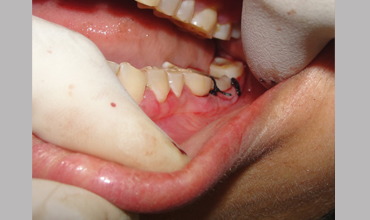

NON SURGICAL MANAGEMENT OF ENDODONTIC LESION AND SURGICAL MANAGEMENT OF PERIODONTIC LESION